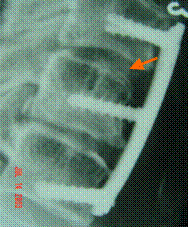

NHAC used in spine fusion operation

(Photos Provided by Professor Cui Fu-Zhai)